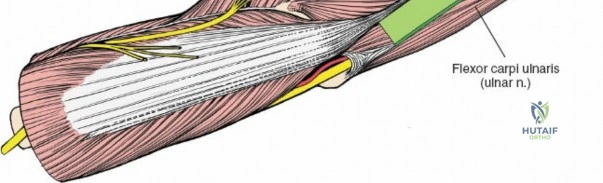

The anterior approach to the radius is an elegant example of utilizing true internervous planes to achieve deep exposure without denervating musculature. Distally, the internervous plane lies between the brachioradialis muscle (innervated by the radial nerve) and the flexor carpi radialis muscle (innervated by the median nerve). Proximally, the plane transitions to lie between the brachioradialis (radial nerve) and the pronator teres muscle (median nerve). Exploiting this plane allows the surgeon to mobilize the entire lateral muscular compartment (the "mobile wad" comprising the brachioradialis, extensor carpi radialis longus, and extensor carpi radialis brevis) away from the anterior flexor compartment.

To confirm the correct plane, look for the superficial branch of the radial nerve. This sensory nerve runs on the undersurface of the brachioradialis muscle. Once the true medial edge of the brachioradialis is found, develop the plane between it and the pronator teres (proximally) or the flexor carpi radialis (distally). Retract the brachioradialis laterally, taking care to keep the superficial radial nerve attached to its undersurface to protect it from traction injury.

With the forearm fully supinated, identify the broad insertion of the supinator on the anterior aspect of the radius. Incise the supinator directly along the line of its insertion onto the bone. It is critical to detach the muscle by dividing its insertion sharply at the bone, rather than splitting the muscle belly, which would risk cutting the PIN.

Proceed with strict subperiosteal dissection, elevating the supinator laterally off the bone. This is one of the rare instances in orthopedic surgery where the safety gained by staying in a subperiosteal plane completely outweighs the theoretical vascular damage to the bone caused by periosteal stripping. The elevated supinator muscle belly now acts as a protective cushion for the PIN.

For fracture fixation, a dynamic compression plate or locking compression plate is applied to the volar surface of the radius. The volar surface provides a flat, mechanically advantageous surface for plating and allows for excellent soft tissue coverage by the overlying muscle bellies upon closure. Ensure that the natural radial bow is meticulously restored during reduction to guarantee full postoperative pronation and supination.